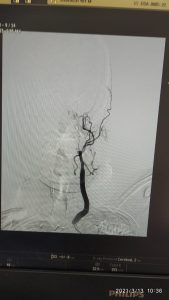

यह व्यक्ति बीमारी के लक्षण आने के छः घंटे के भीतर हॉस्पिटल में पहुँचे और यहाँ पर डीएसए मशीन की मदद से नूरोरेडीआलॉजी की टीम ने आकस्मिक उपचार प्रदान किया और आज मरीज़ पूर्ण तौर पर स्वस्थ है। आईजीएमसी के डॉक्टर्स और मशीन के माध्यम से मरीज की जान बचाई गई है।इस केस को लेकर आईजीएमसी की पीठ थपथपाई जा रही है।